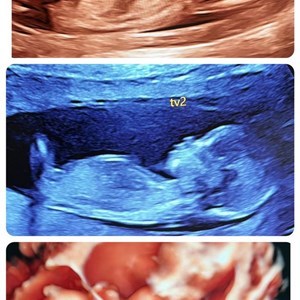

Dobbelt lykke ❤️💙 2 små fine mennesker godt på vej. Tveæggede tvillinger uge 14+1. Begg...